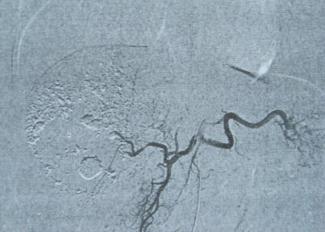

以下是肝动脉造影示肝血管瘤栓塞前后对比图

肝动脉栓塞后血管瘤的供血动脉被阻断